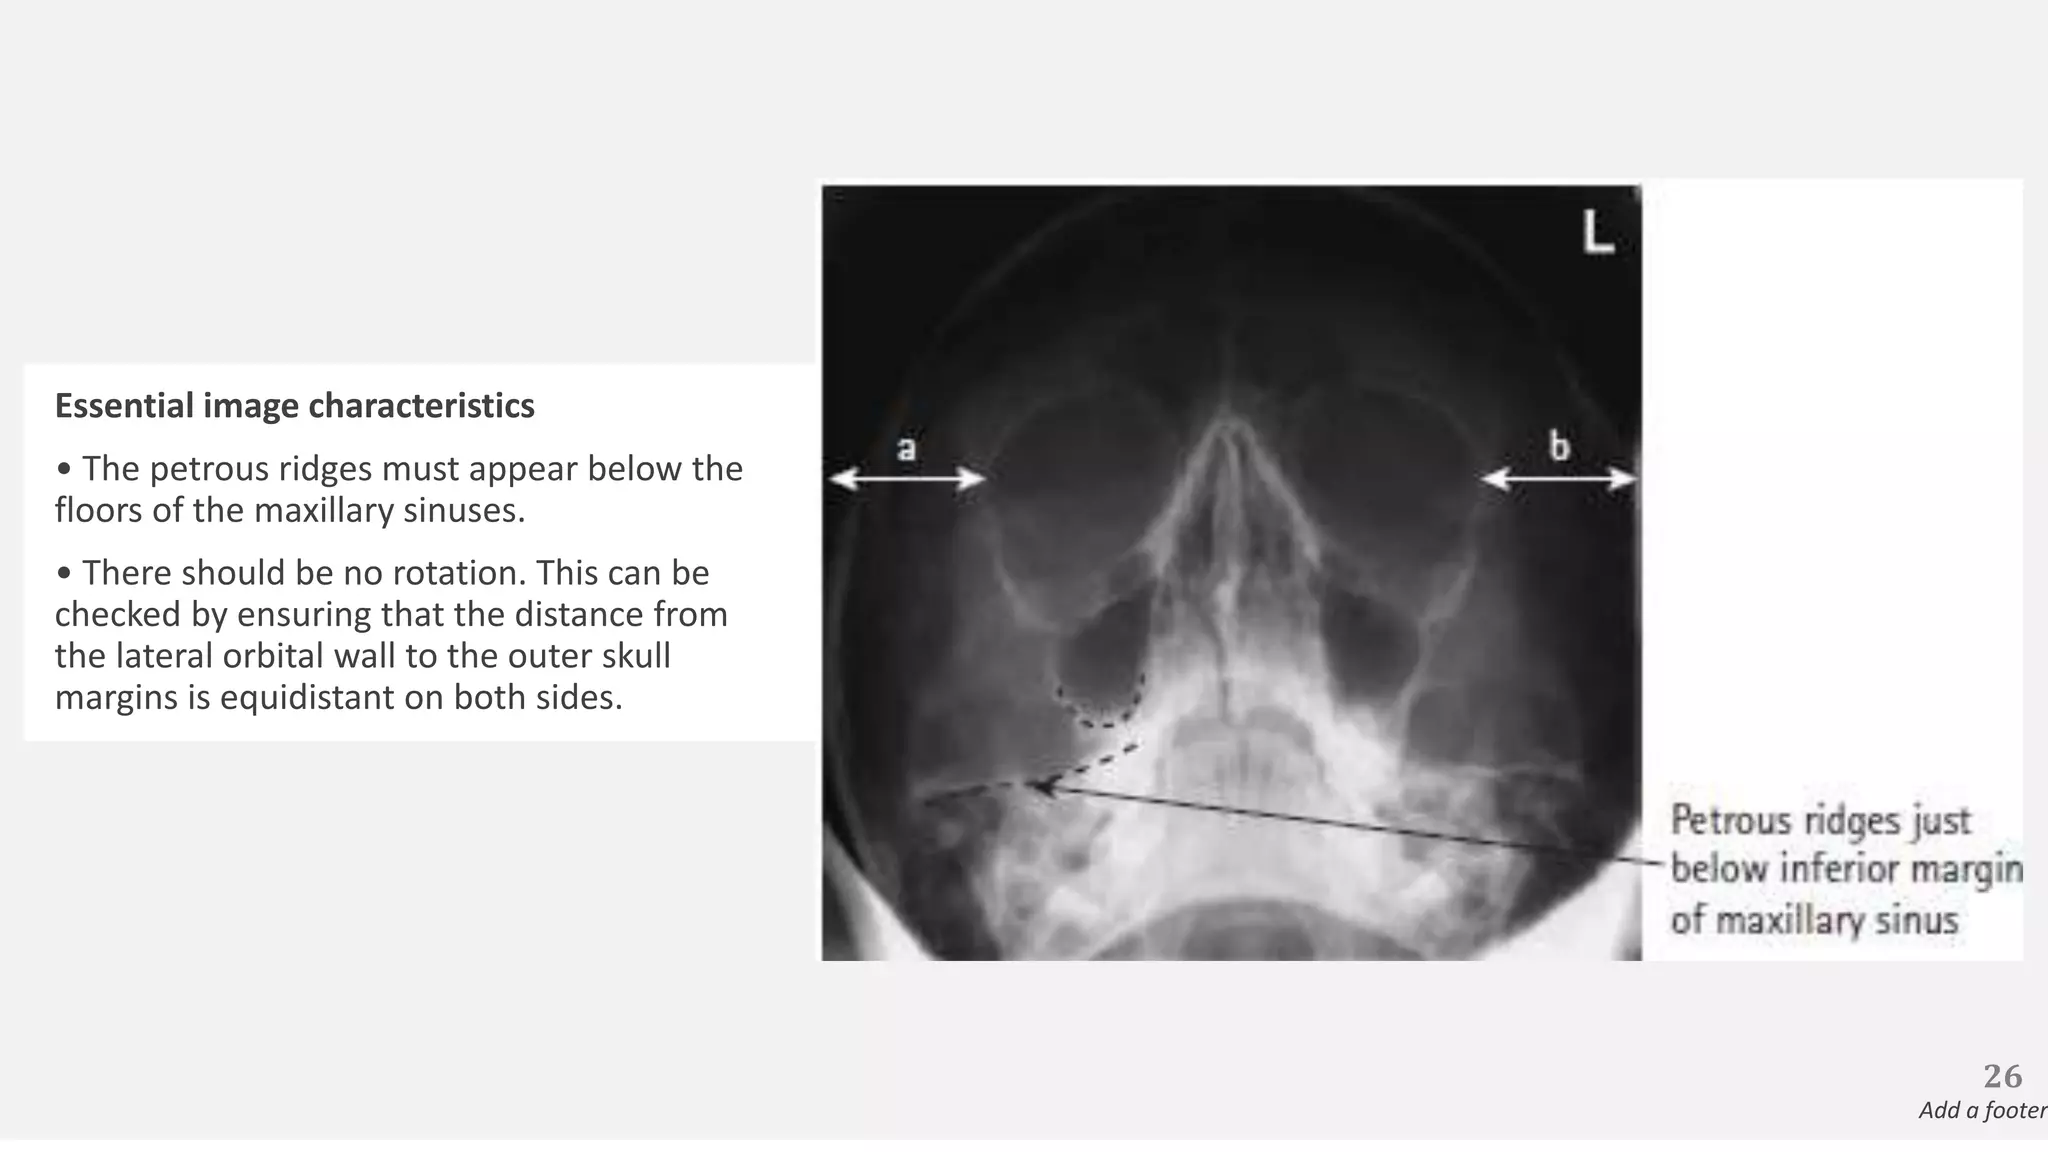

Essential image characteristics

• The petrous ridges must appear below the

floors of the maxillary sinuses.

• There should be no rotation. This can be

checked by ensuring that the distance from

the lateral orbital wall to the outer skull

margins is equidistant on both sides.